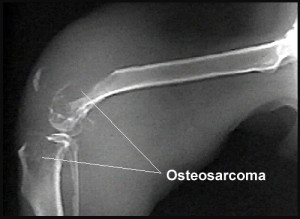

Osteosarcoma In Dogs

What Is Dog Osteosarcoma?